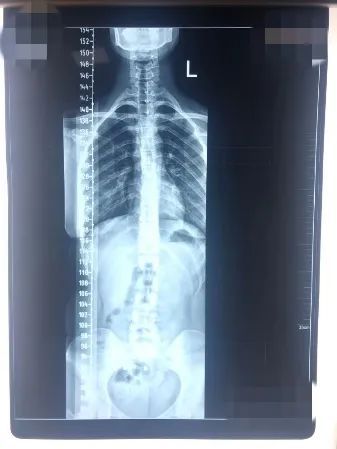

青少年患者治疗前

青少年患者治疗后

患者的脊柱侧弯度数得到改善